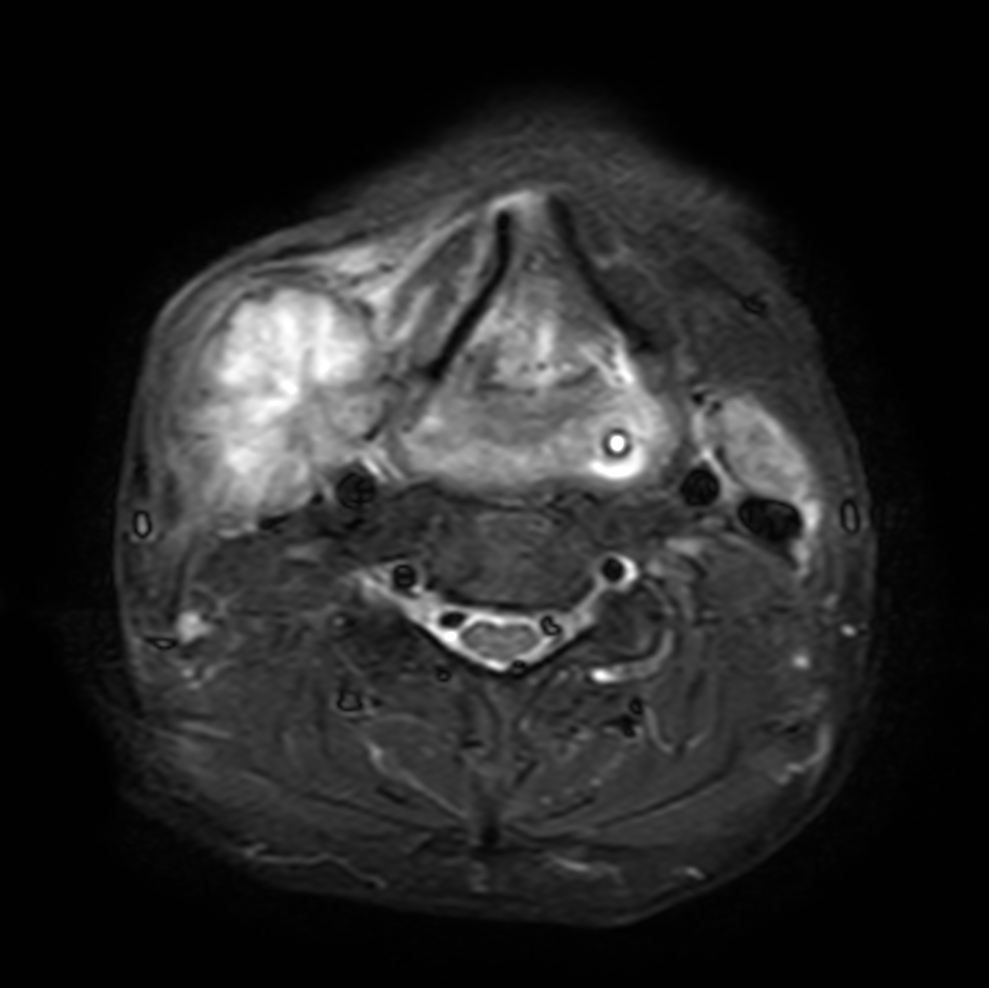

Axial T1w TSE

Axial T2w TSE

Axial STIR TSE